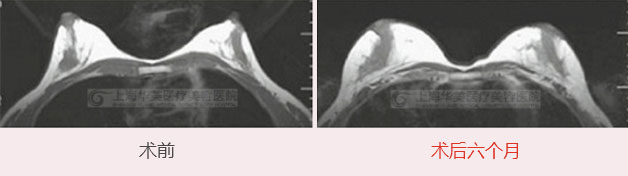

通过MRI照片可以确认手术后脂肪安全成活的情况